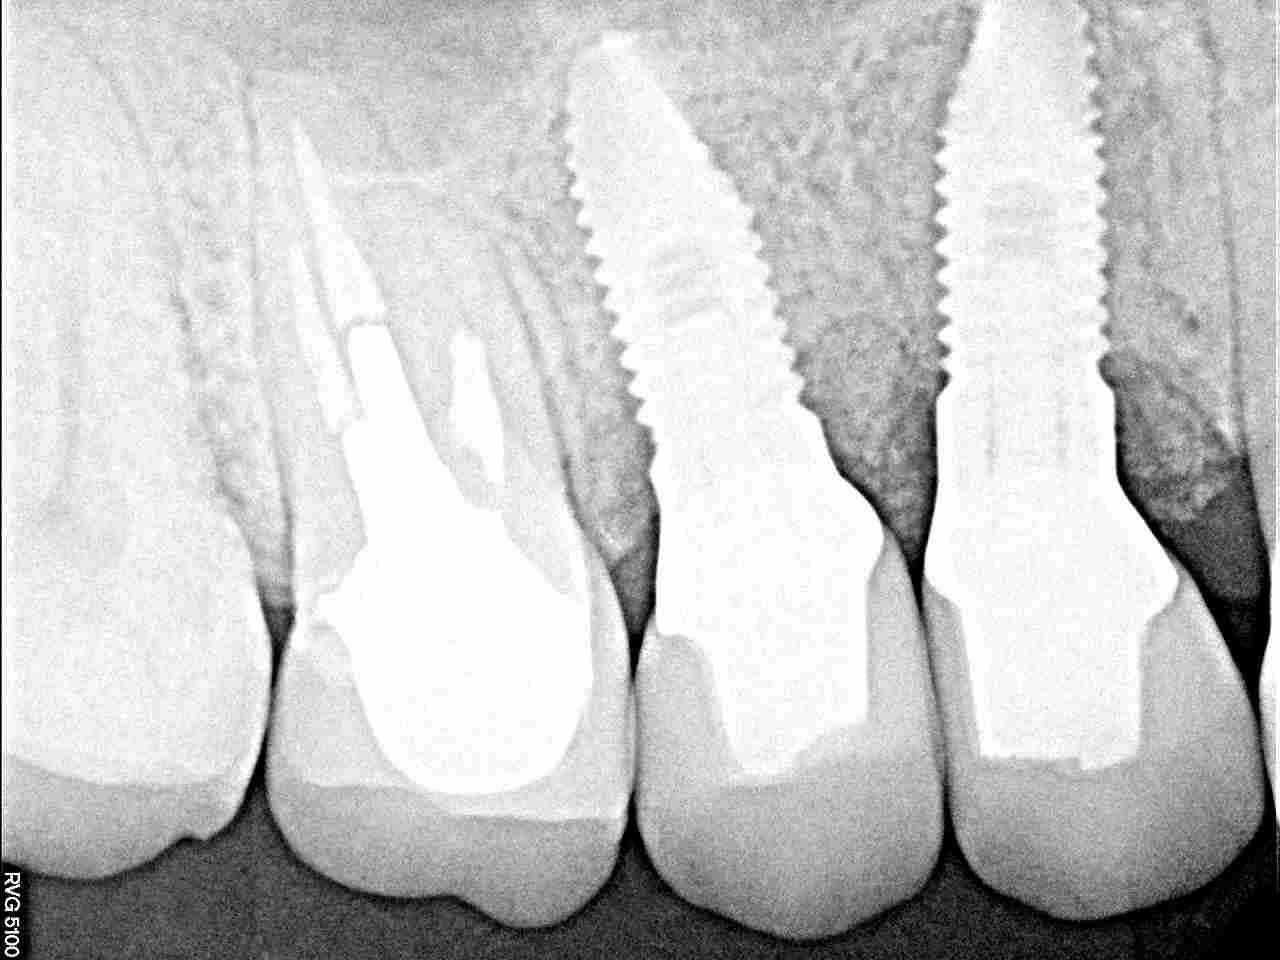

インプラントの最終補綴へ 埋入より3か月後になります|お知らせ |広島市安佐南区の歯科医院 インプラントの最終補綴へ 埋入より3か月後になります トップ お知らせ・ブログ お知らせ インプラントの最終補綴へ 埋入より3か月後になります インプラントの最終補綴へ 埋入より3か月後になります このように傷が治ります きれいに治っています カスタムアバットメントにて作成しています このように立ち上げています レントゲンにてもソーサライゼーションの起こりにくい埋入深さになります オールセラミックにて作成しています 抜歯窩にもドリリング時には足を取られ、上顎洞も持ち上げながら、 スペースが狭くなっていることもあり、5番は少し傾斜埋入となりました Web診療予約 初めての方へ 選ばれ続ける理由 院内設備について 歯が痛いしみる一般歯科 歯がぐらぐらする歯周病 健康な歯を保ちたい予防歯科 子供の虫歯予防をしたい小児歯科 銀歯をセラミックに審美歯科 白い歯を目指しませんか?ホワイトニング 矯正専門医がいるので安心矯正歯科 抜けた歯を補いたいインプラント・入れ歯 医院案内 スタッフ紹介 メリィハウス歯科クリニックオフィシャルホームページ ラベンダー歯科クリニックオフィシャルホームページ お知らせ・ブログ ホーム 診療科目 一般歯科 歯周病治療 予防治療 小児歯科 審美治療 ホワイトニング 矯正歯科 入れ歯・インプラント マウスピース矯正 初めての方へ 院長・スタッフ 設備紹介 医院案内・アクセス メニューを閉じる